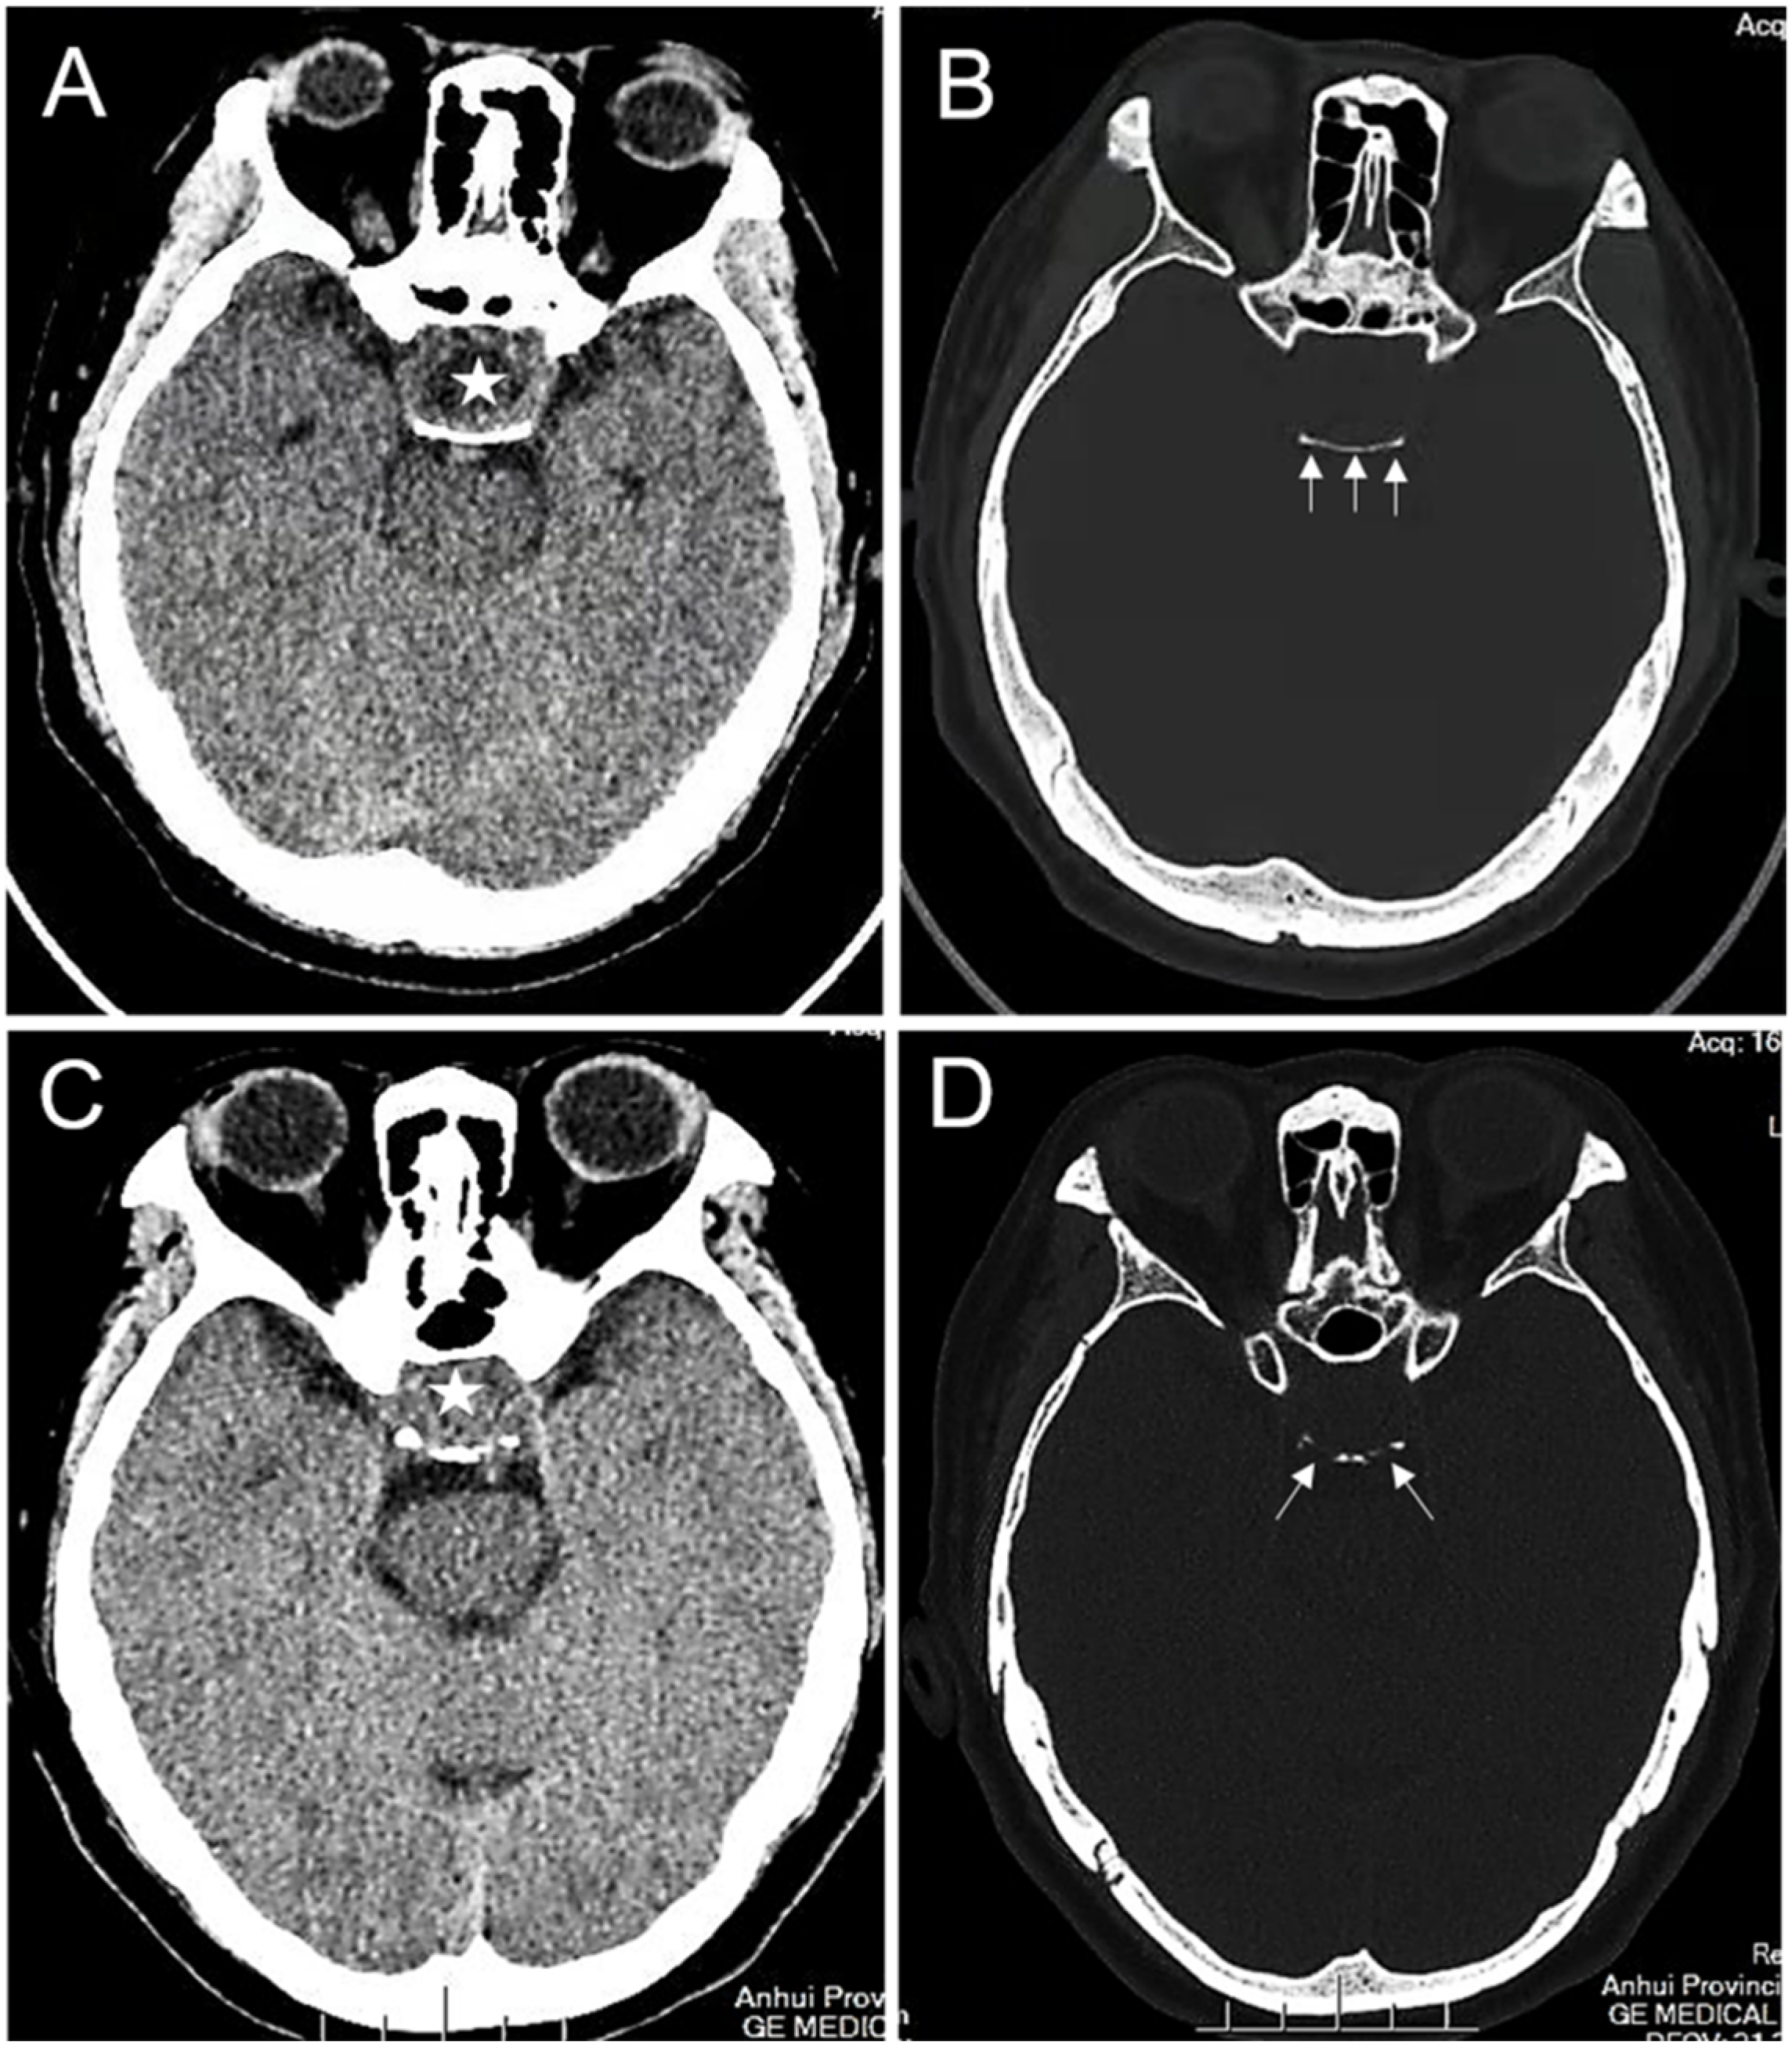

| Erosion of the dorsum sellae bone | ||||

| Yes | 30 (41.67%) | 82 (77.36%) | 23.41 | <0.0001 |

| No | 42 (58.33%) | 24 (22.64%) | ||

| Rich blood supply to the tumor | ||||

| Yes | 27 (37.50%) | 84 (79.25%) | 31.830 | <0.0001 |

| No | 45 (62.50%) | 22 (20.75%) | ||